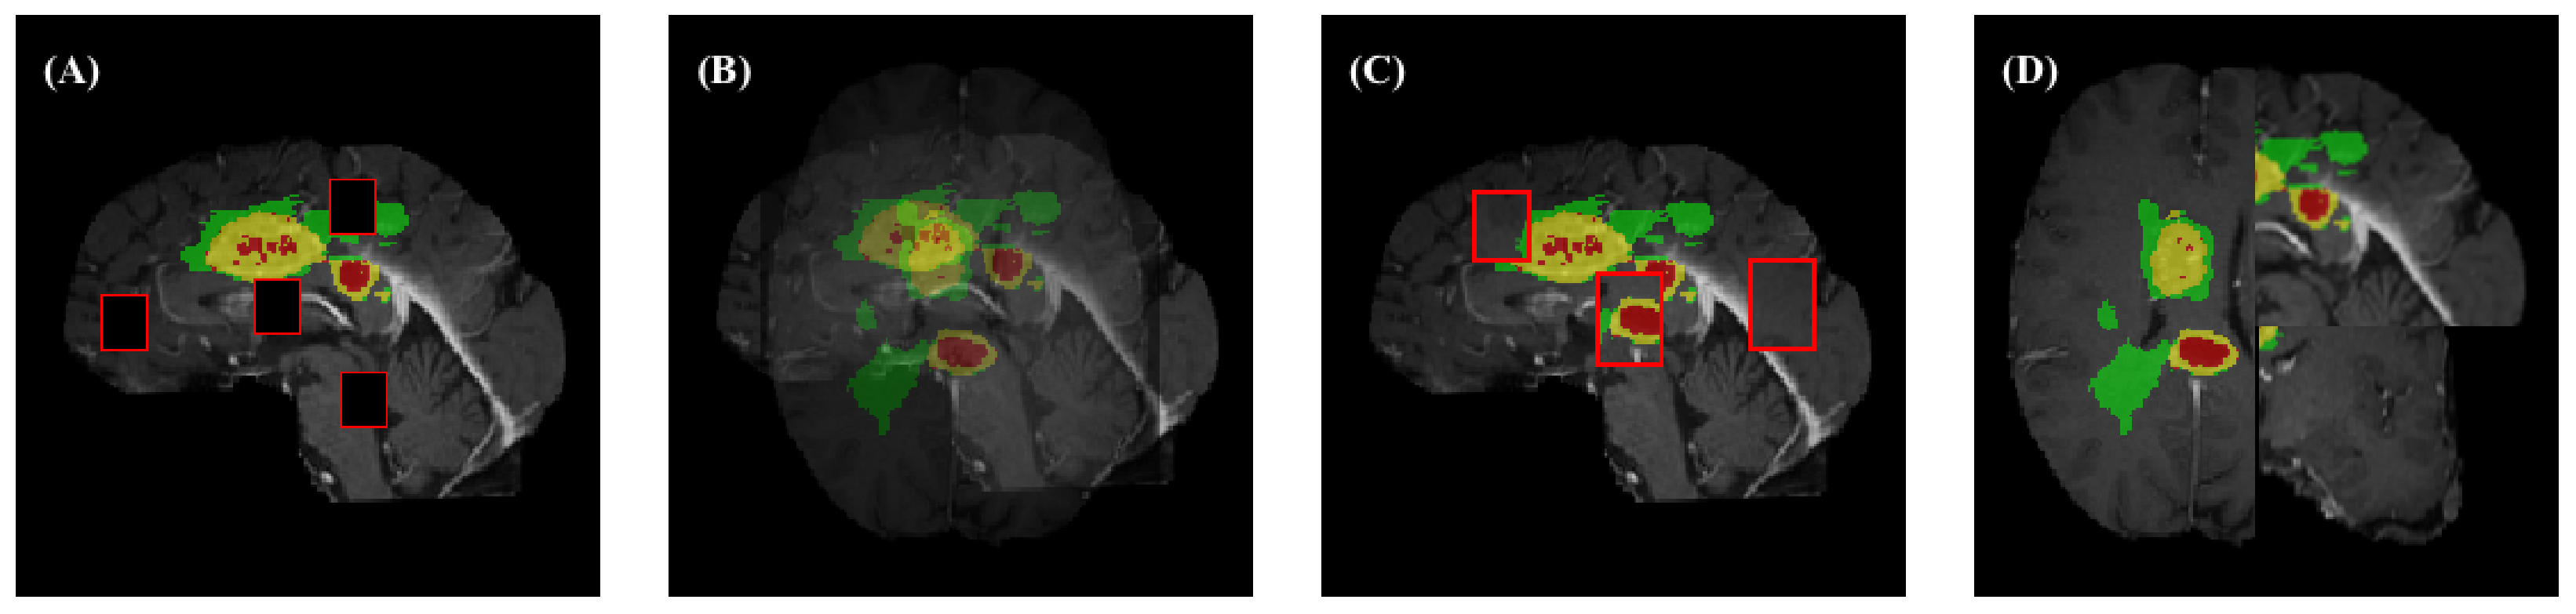

4.2. Segmentation Results

5. Discussion